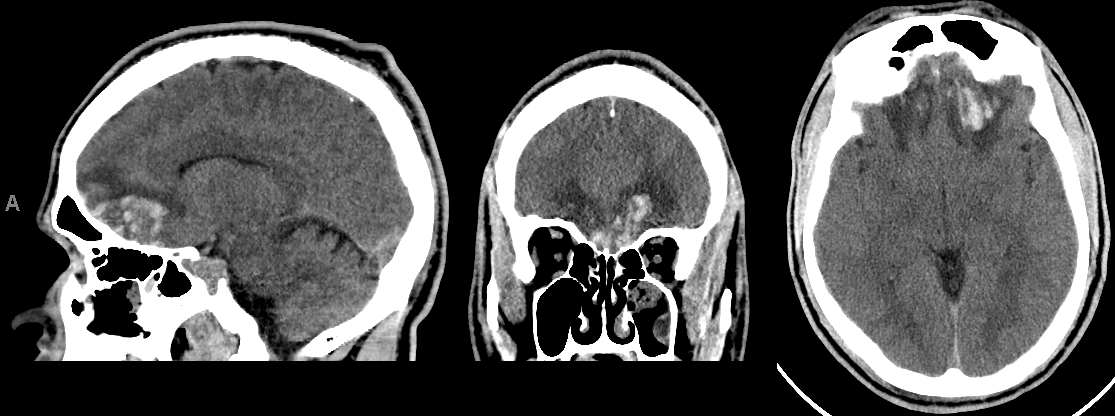

Example Case: Bifrontal Contusions

A 32 year old male was brought to the emergency department escorted by police after being found on the ground on an early Sunday morning. He had a large fresh bruise on the back of his head, and had no recollection of what happened. He had no wallet and a high serum alcohol level.

Additional history from his girlfriend suggested the patient was impulsive at baseline and frequently got into fights.

Initial exam showed a well developed, muscular male who was lying quietly, following suggestions passively, and had no focal weakness and had intact speech and comprehension. The patient also complained of loss of taste and smell.

Over the next 3 days he had large swings in mood and at times took aggressive tones to family and hospital staff.

CT head showed bifrontal contusions.

Summary: This is a classic presentation of a traumatic contrecoup injury to bilateral orbitofrontal areas. The change in baseline behavior with emotional lability is often seen with orbitofrontal lesions, and the loss of smell and taste helps with localization.